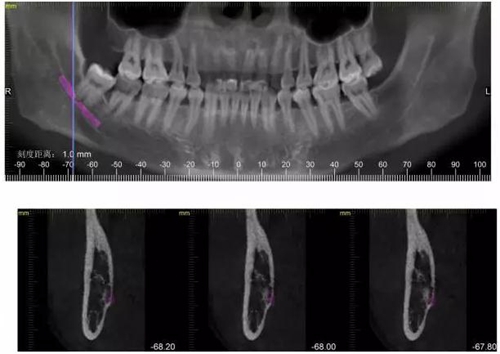

CBCT神經(jīng)管標(biāo)線,可以看到標(biāo)線不能連續(xù),中間被阻斷。

1500632983_511898.jpg